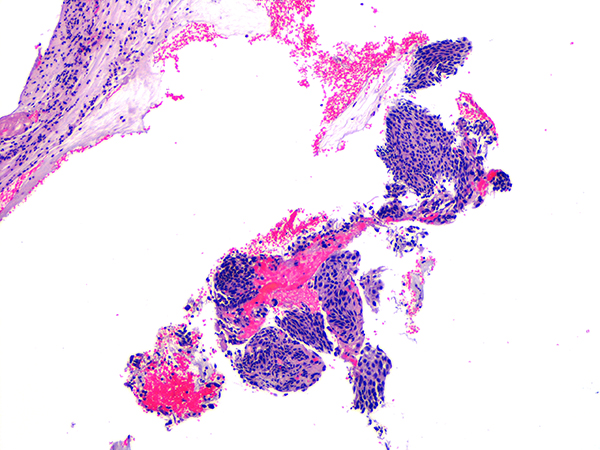

Case 3

Soft Bx CIN 2-3 10x - Low Power